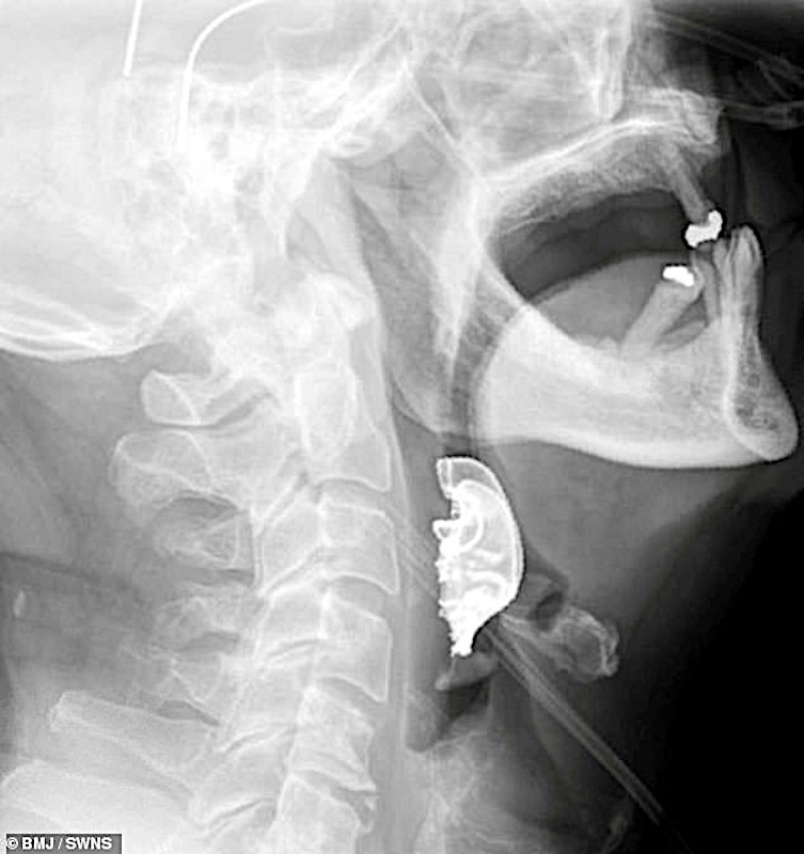

Satu prosedur diagnostik untuk melihat ke dalam kerongkong pesakit itu dijalankan sebelum satu objek berbentuk bulan sabit ditemui berdekatan peti suaranya, kemudian disahkan adalah gigi palsu lelaki tersebut.

Selepas dimaklumkan tentang penemuan tersebut, pesakit berkenaan baru sedar gigi palsunya hilang selepas menjalani pembedahan lapan hari sebelum itu. Gigi palsu itu berjaya dikeluarkan melalui satu pembedahan kecemasan dan pesakit itu dibenarkan pulang enam hari kemudian. – Agensi